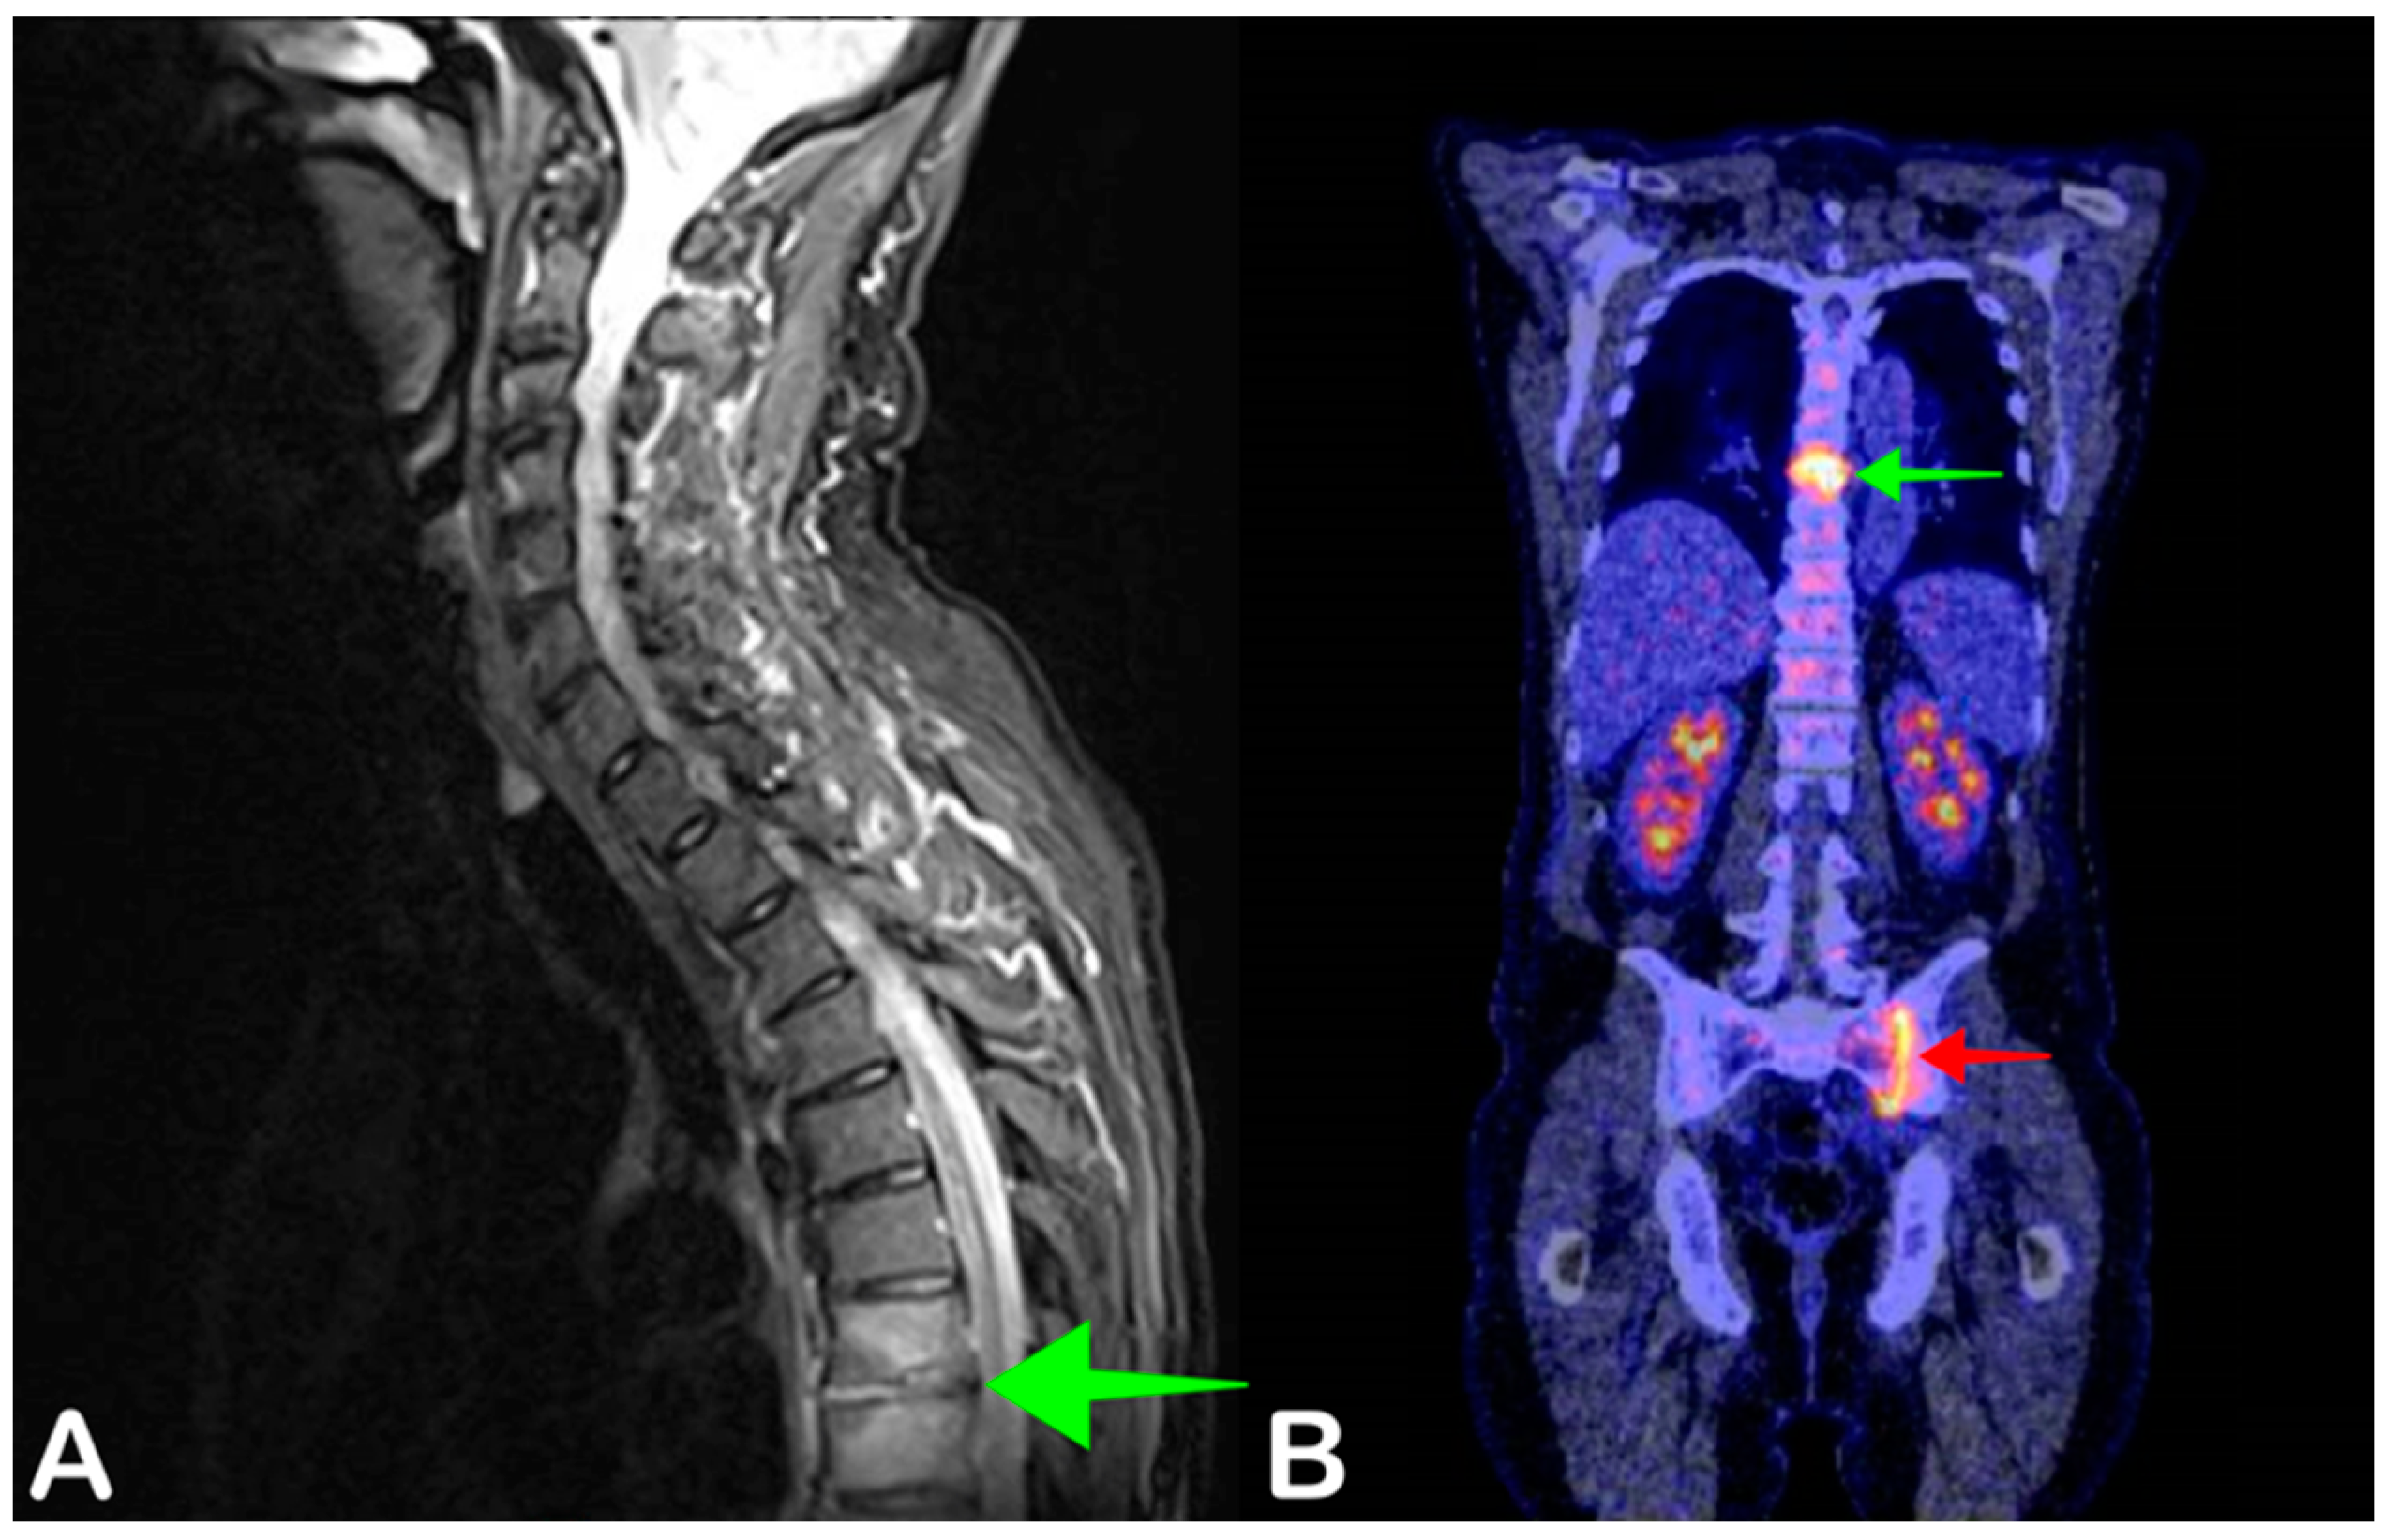

2.5. Spondylodiscitis

- Smids, C.; Kouijzer, I.J.E.; Vos, F.J.; Sprong, T.; Hosman, A.J.F.; De Rooy, J.W.J.; Aarntzen, E.H.J.G.; De Geus-Oei, L.-F.; Oyen, W.J.G.; Bleeker-Rovers, C.P. A comparison of the diagnostic value of MRI and 18F-FDG-PET/CT in suspected spondylodiscitis. Infection 2017, 45, 41–49. [Google Scholar] [CrossRef] [Green Version]

- Altini, C.; Lavelli, V.; Niccoli-Asabella, A.; Sardaro, A.; Branca, A.; Santo, G.; Ferrari, C.; Rubini, G. Comparison of the Diagnostic Value of MRI and Whole Body 18F-FDG PET/CT in Diagnosis of Spondylodiscitis. J. Clin. Med. 2020, 9, 1581. [Google Scholar] [CrossRef]